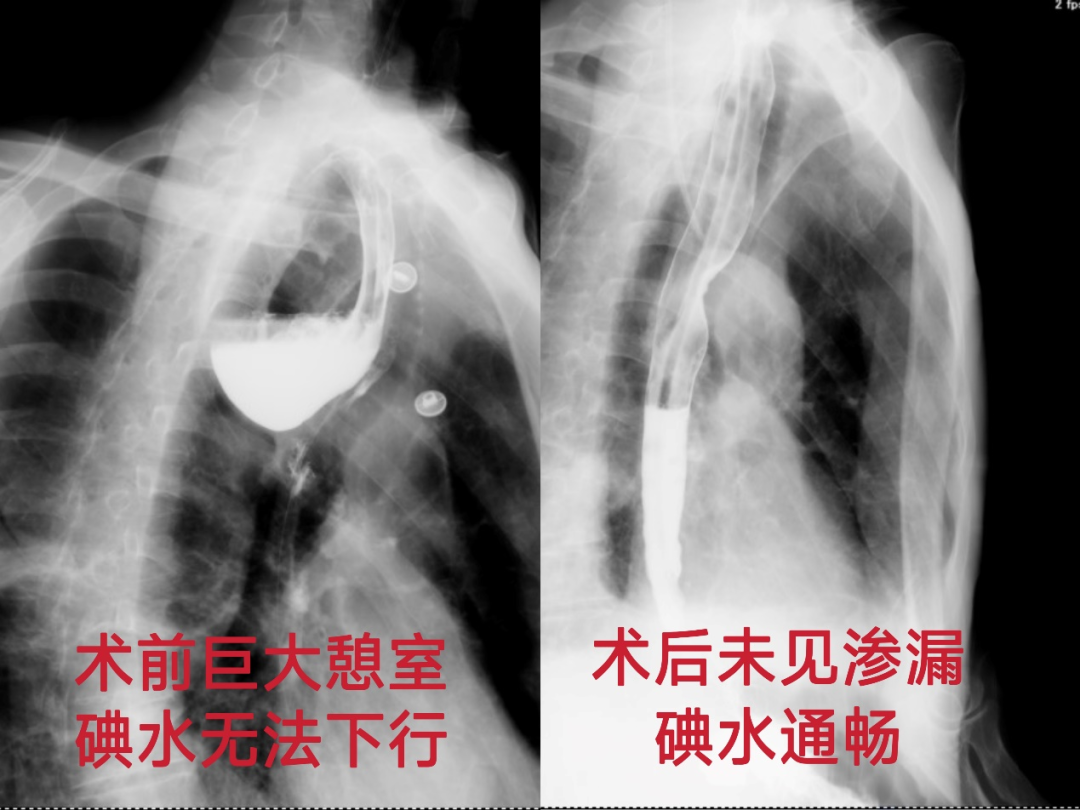

术后,胸外科医护团队为张先生制定了阶梯式精细化营养支持方案及围术期并发症管理计划。术后一周,碘水造影显示患者食管通畅,吻合口完整无渗漏;颈部切口愈合后仅留下一条细微痕迹,几乎隐匿于皮肤纹理之中,真正实现了疾病治愈与外观维护的双重目标。